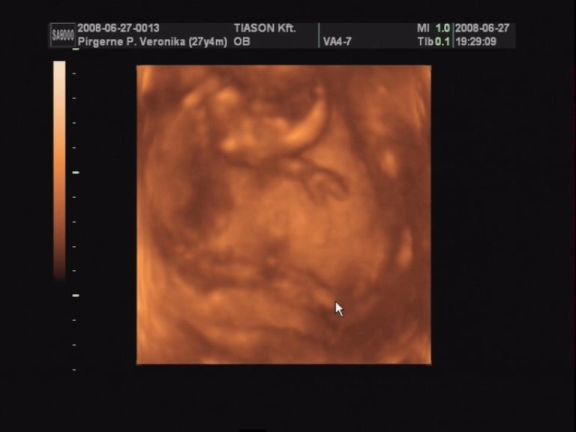

Csodálatos élmény volt az uh!

Nem lehetett még látni, kisfiú vagy kislány van odabent, de nagyon nagyon jó lett a videó. Rengeteget mozgott, rugdalózott, kitámasztotta magát, kalimpált a kezével, iszonyú jó volt. Még a pofijáról is van kép, az is egészen jól látszik.

Egyszóval nagy a boldogságunk, gondolhatjátok. :lol:

Próbálok majd egy két képet levarázsolni a videóról és felrakni hétvégén.